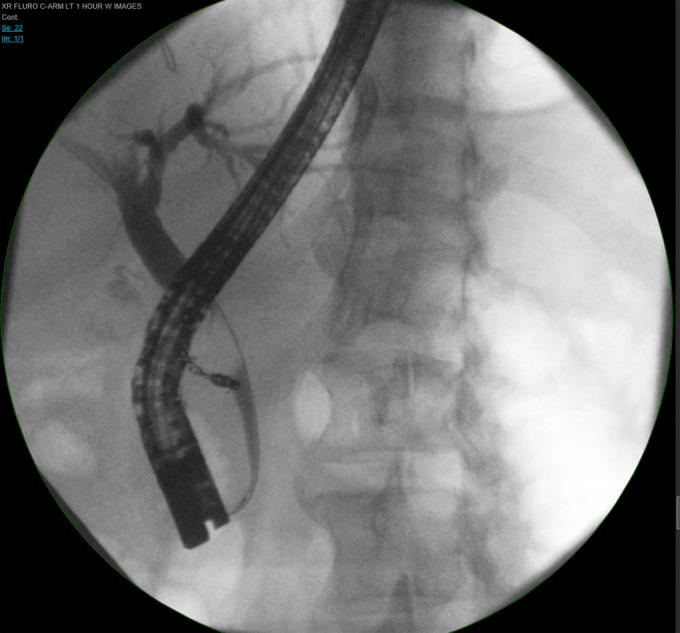

成功微创治疗导致肝外胆管受压的胃十二指肠动脉假性动脉瘤

Successful Minimally Invasive Management of a Gastroduodenal Artery Pseudoaneurysm Causing Extrinsic Bile Duct Compression.

Gastroduodenal artery (GDA) pseudoaneurysms are rare clinical entities that typically develop in the setting of chronic inflammation of the pancreas, although idiopathic pseudoaneurysms can occur. Although GDA pseudoaneurysms carry the risk of rupture with resultant hemorrhage, they seldom are reported to cause biliary obstruction. We report a unique case of biliary obstruction secondary to extrinsic compression of the bile duct by a GDA pseudoaneurysm successfully managed by nonoperative means.

摘要

胃十二指肠动脉(GDA)假性动脉瘤是一种罕见的临床病症,通常在胰腺慢性炎症的背景下发生,不过也可能出现特发性假性动脉瘤。尽管GDA假性动脉瘤有破裂并导致出血的风险,但很少有报道称其会引起胆管梗阻。我们报告了一例独特的病例,该病例为GDA假性动脉瘤对胆管造成外部压迫继发胆管梗阻,通过非手术方法成功治愈。